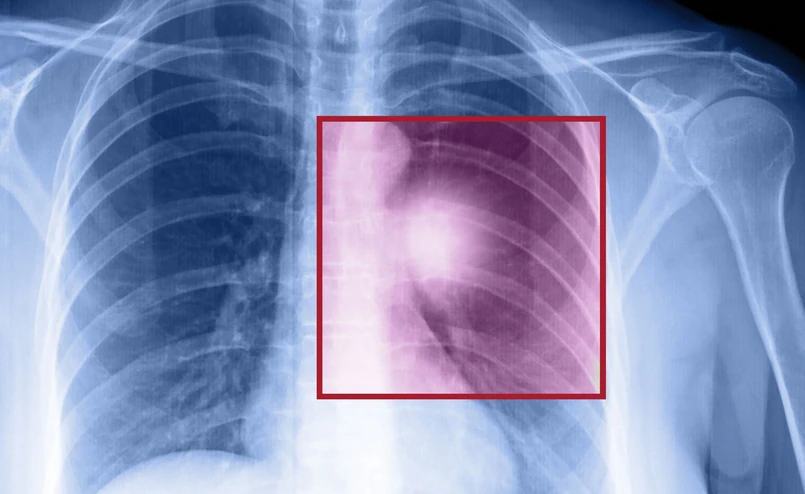

- Rak płuca jest najczęstszym nowotworem złośliwym. Szacujemy, że w Polsce co roku mamy ponad 22 tys. nowych zachorowań na ten nowotwór. Jest to również zabójca numer jeden z przyczyn nowotworowych zarówno wśród mężczyzn, jak i wśród kobiet – ocenił prof. Rodryg Ramlau, kierownik Katedry i Kliniki Onkologii Uniwersytetu Medycznego im. Karola Marcinkowskiego w Poznaniu. 80 proc. przypadków tego nowotworu stanowi tzw. niedrobnokomórkowy rak płuca.

Wysoka śmiertelność pacjentów z rakiem płuca wynika z tego, że jest on rozpoznawany przeważnie w stadium zaawansowanym. - To jest nowotwór, który w momencie rozpoznania jest na tyle zaawansowany, że możliwości postępowania operacyjnego, dającego nadzieję na wyleczenie, są znikome. Operacji poddawanych jest jedynie 15-20 proc. chorych. Dlatego jesteśmy tym chorym zobowiązani poszukiwać innych, nowoczesnych metod terapii – zaznaczył onkolog.